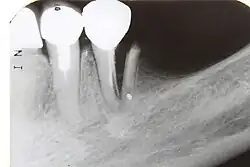

Pulpal obliteration

4–24% of traumatized teeth will have some degrees of pulpal obliteration that is characterized by the loss of pulpal space radiographically and yellow discolouration of the clinical crown. No treatment is needed if it is asymptomatic. Treatment options will be extraction for symptomatic primary tooth. For symptomatic permanent tooth, root canal treatment is often challenging because the pulp chamber is filled with calcified material and the drop-off sensation of entering a pulp chamber will not occur.[44]